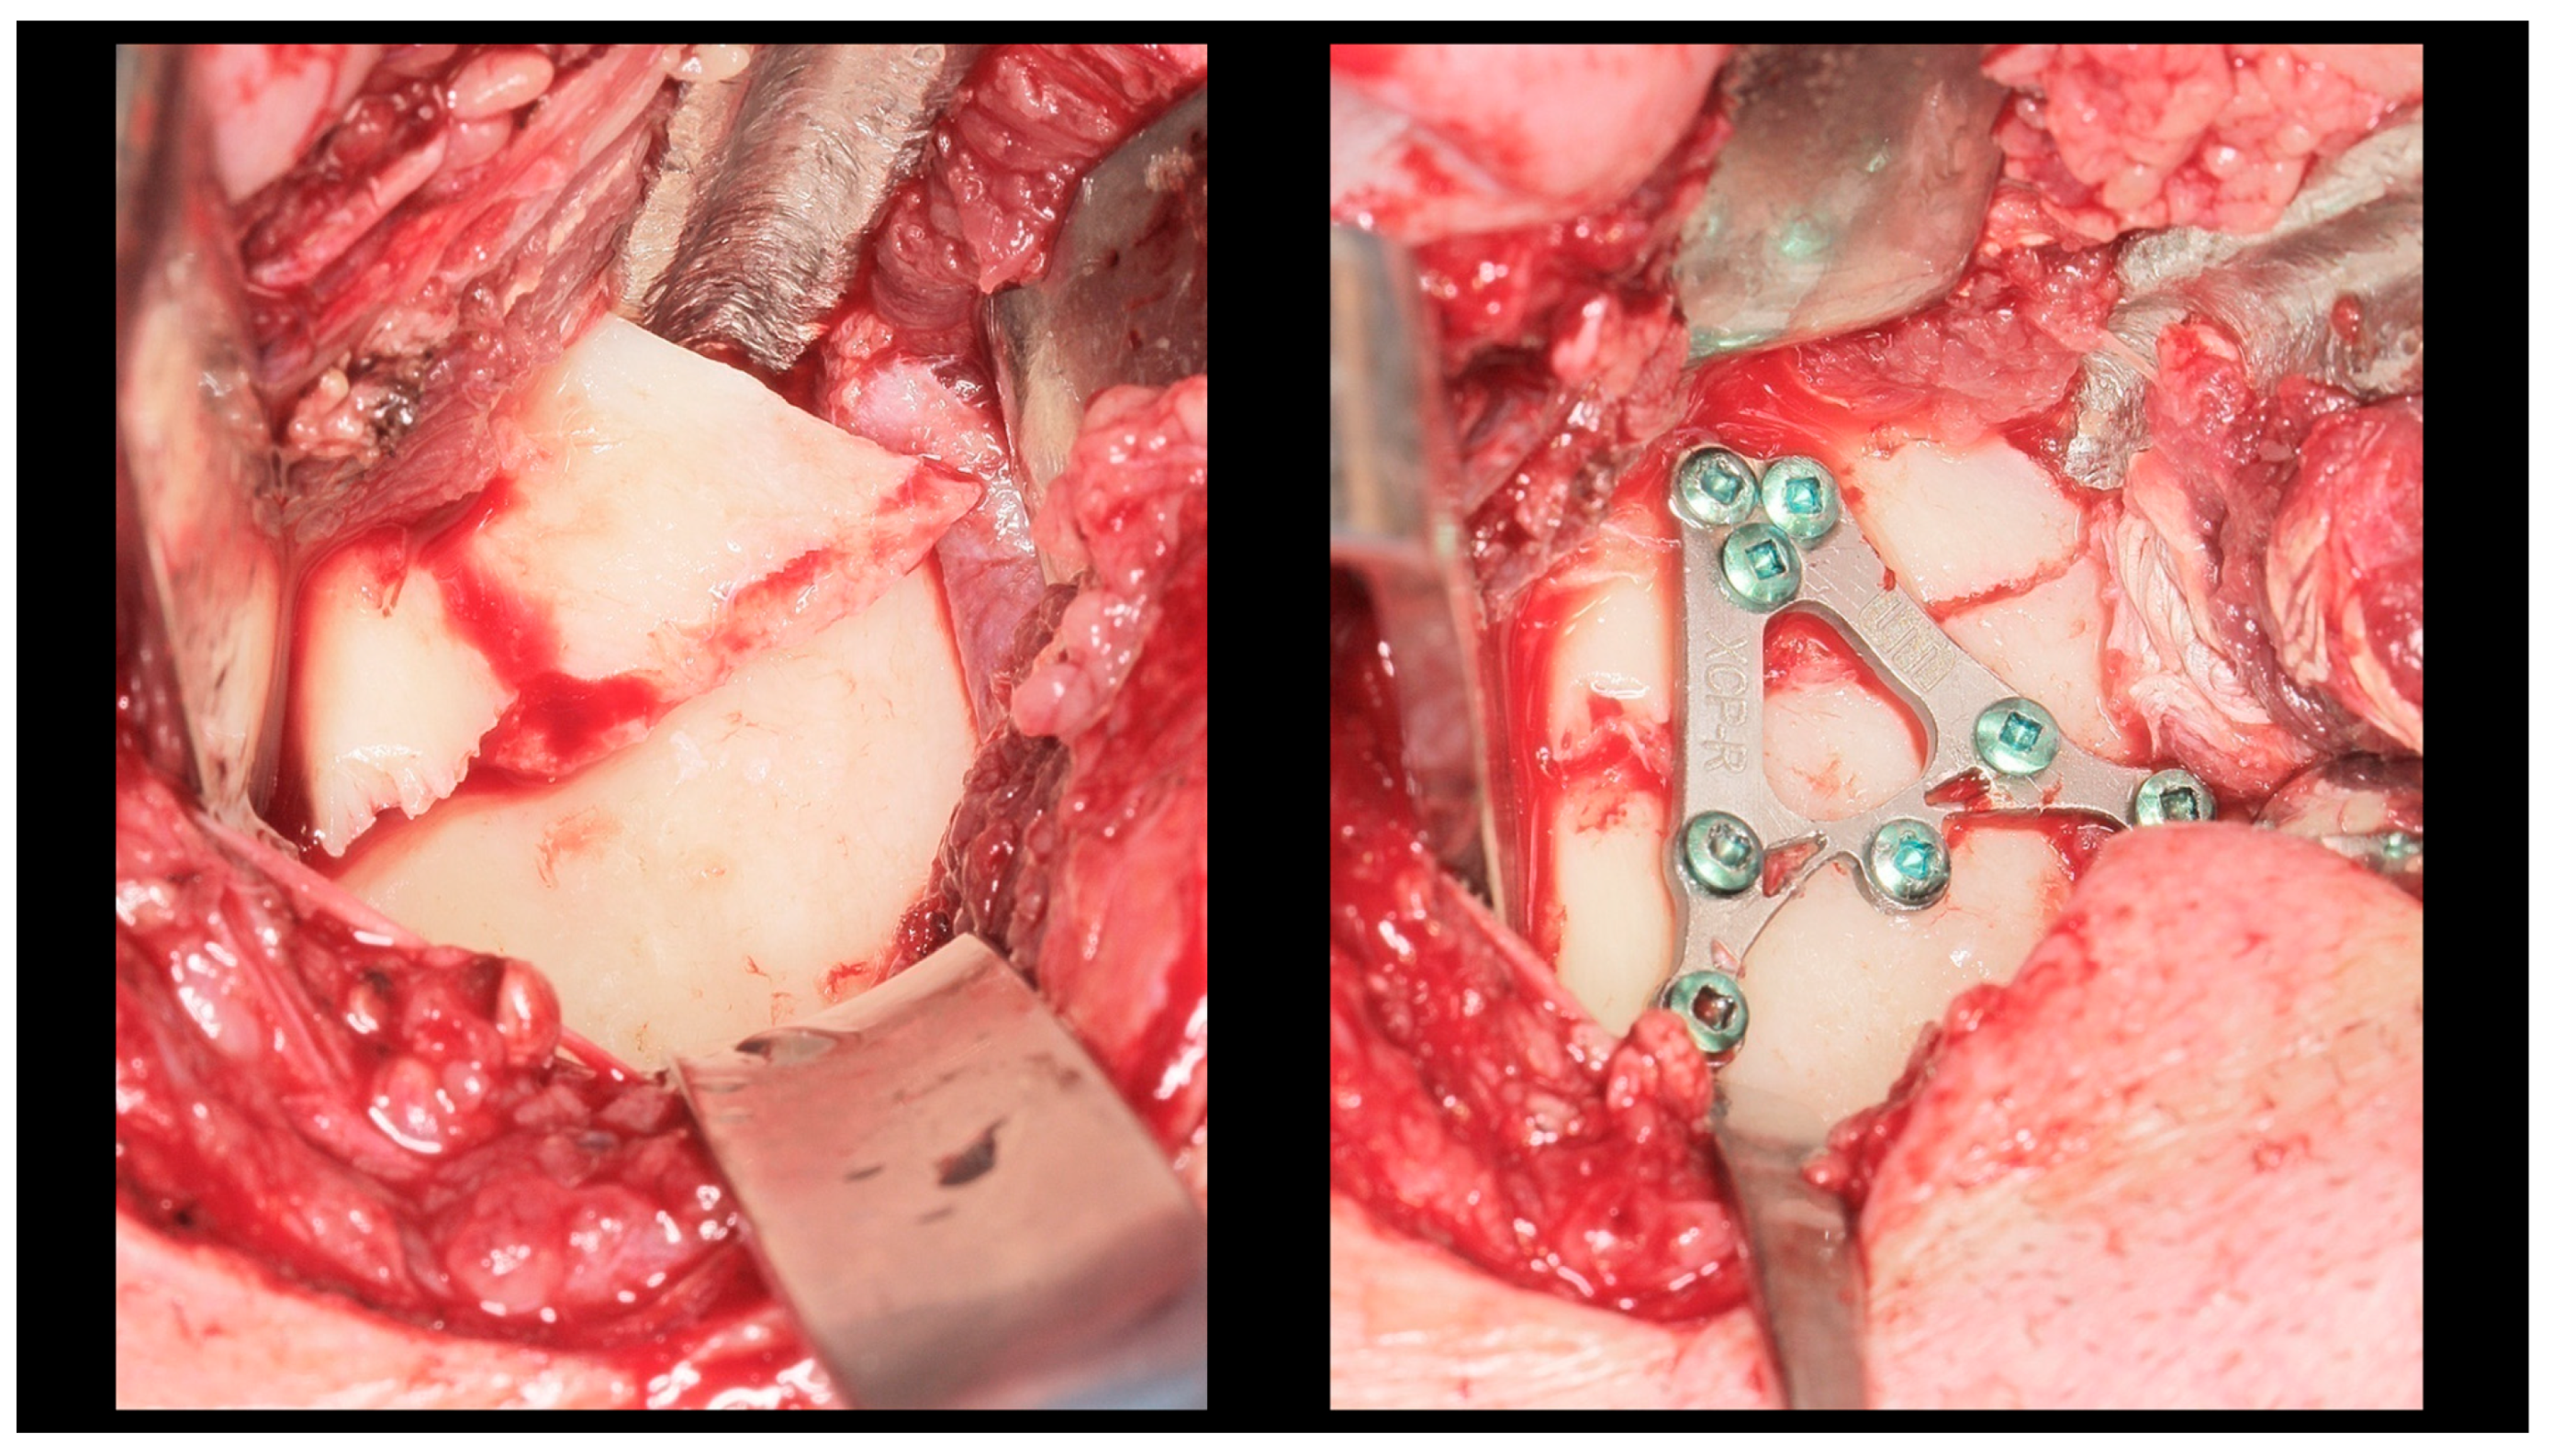

| ACP | ‘’A’’—shape condylar plate |

| XCP | ‘’X’’—shape condylar plate |